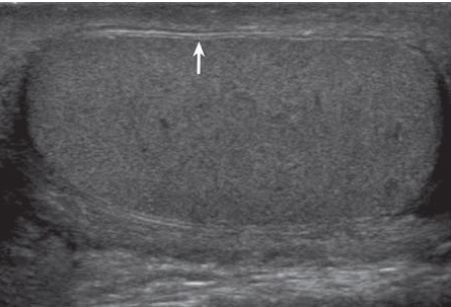

- Rách bao trắng tinh hoàn (Tunica Albuginea): bao trắng bình thường có hình ảnh 2 lớp tăng hồi âm chạy song song với nhau bao quanh tinh hoàn (Hình3). Khi có dấu hiệu mất liên tục của bao trắng có nghĩa là rách bao trắng hay vỡ tinh hoàn (Hình4). Tuy nhiên khi có khối máu tụ lớn ngoài tinh hoàn thì siêu âm hạn chế trong việc phát hiện dấu hiệu rách bao trắng này.

- Bất thường đường viền tinh hoàn: khi tinh hoàn vỡ, sự đùn ra của nhu mô tinh hoàn qua chỗ vỡ sẽ tạo nên sự di thường của một bề mặt tinh hoàn bắng phẳng bình thường (Hình5).. Khi có khối máu tụ lớn ngoài tinh hoàn hay khối máu tụ lớn ở vùng bìu làm khó phát hiện dấu hiệu rách bao trắng tinh hoàn thì hình ảnh này là dấu hiệu gián tiếp của vỡ tinh hoàn